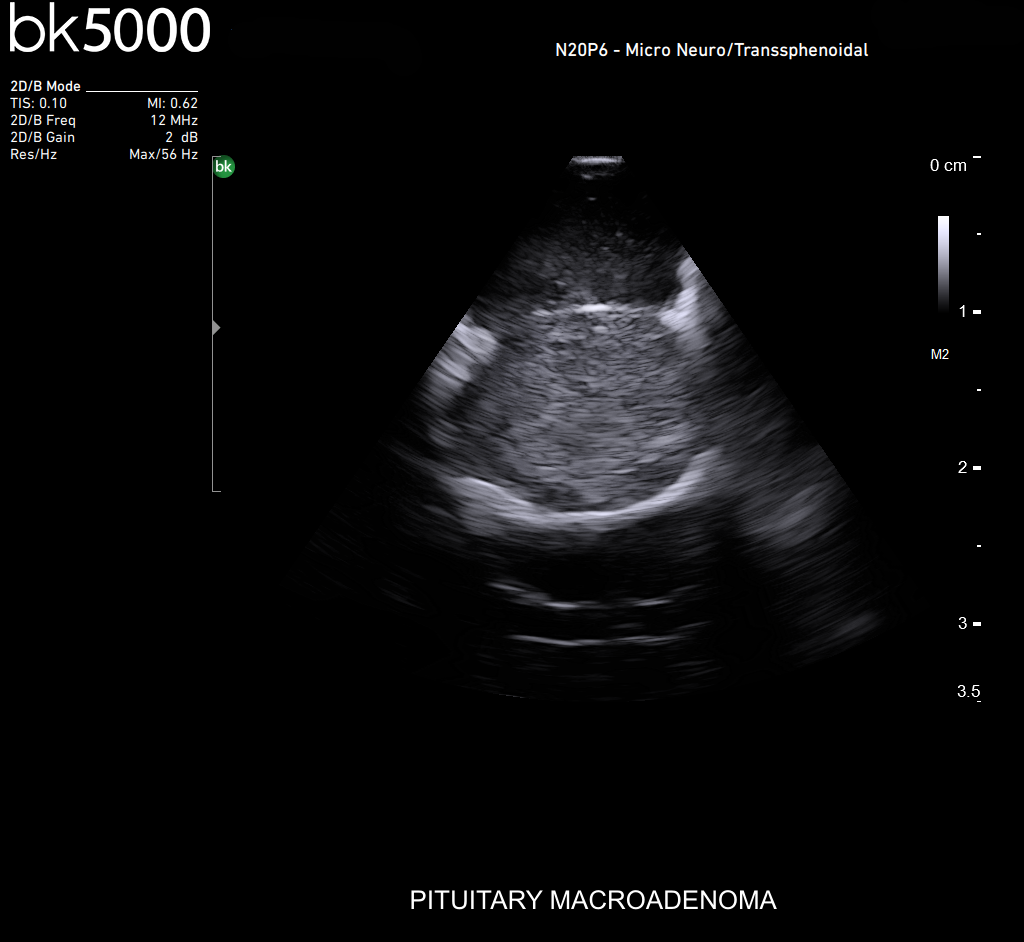

Ultrasound can improve neurosurgical procedures by helping you navigate and identify lesions and anatomical structures in real-time. This is particularly important as the data obtained from a preoperative CT or MRI scan can be outdated at the time of surgery. The bk5000 neurosurgical system provides the highest quality images that allow you to clearly see the margins of a lesion and to determine the best course of action. Using advanced graphics processing technology, this powerful system provides immediate, auto-optimized images that allow you to see the information you need, faster.

The specialized, high-resolution, sterilizable neurosurgery transducers enable you to obtain detailed images of the brain and spinal cord. They have a convenient Smart™ button that lets you activate the transducer, then freeze, store or print the images at the press of a button. Disposable, easy-to-use needle guides assist with targeting lesions.